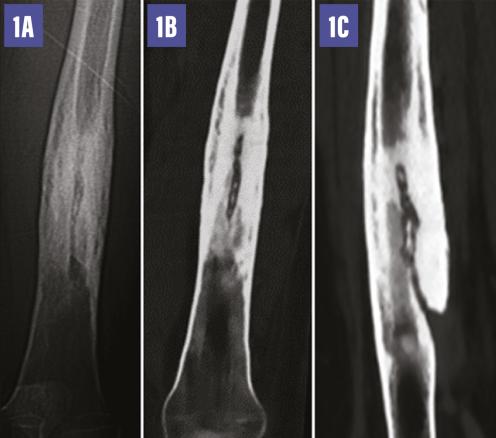

Une radiographie standard complétée par un scanner (fig. 1 ) met en évidence un épaississement cortico-périosté de la diaphyse fémorale, une condensation de l’os médullaire centrée par une ostéolyse linéaire décrivant un trajet fistuleux qui alimente une collection abcédée des parties molles renfermant des séquestres osseux (fig. 2 ). Le diagnostic d’ostéomyélite chronique est retenu.

Une radiographie standard complétée par un scanner (